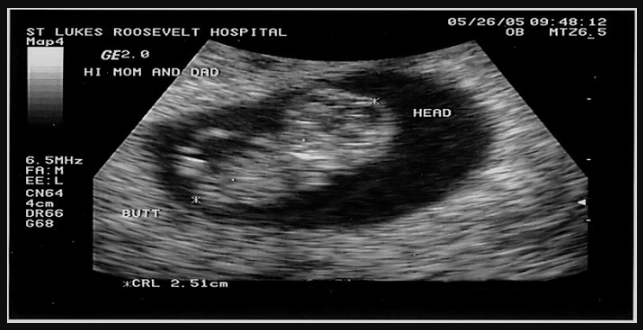

Siêu âm thai 9 tuần cho thấy sự thay đổi mạnh mẽ về kích thước và trọng lượng. Bé sẽ có chiều dài khoảng 2,5cm và cân nặng 2g. Các bộ phận trong cơ thể dần hoàn thiện hơn. Đây cũng là thời điểm bào thai, các mô và cơ bắt đầu phát triển nhanh chóng.

Theo các chuyên gia, thai nhi 9 tuần tuổi có nhịp tim trung bình vào khoảng 170 lần/nhịp và có thể tăng lên 180 lần/nhịp nếu bé cử động trong bụng mẹ.